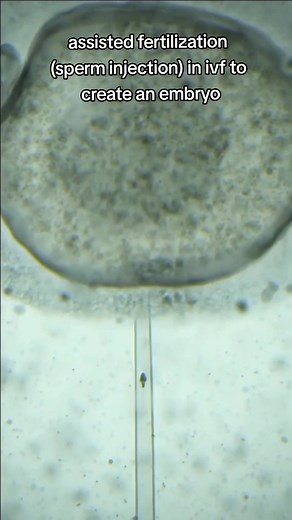

sperm injection or icsi revolutionized ivf to overcome human infertility #ivf #infertility #ttc #icsi #foryour #yourpage #xyzbca video cred sk_beats_editor

TikTok

stevenpaltermd

已浏览 1640万 次

2023年10月30日